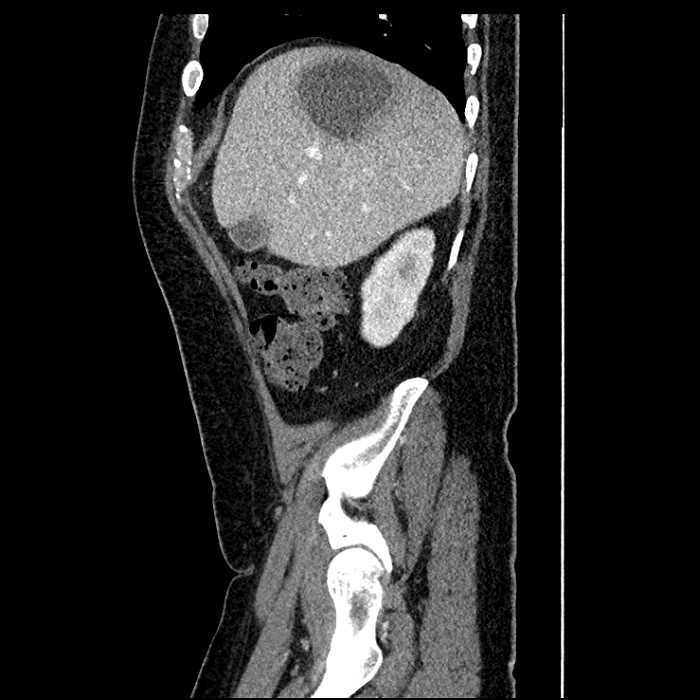

Age: 63

Sex: Male

Indication: Abdominal pain

• Large fluid density structure in hepatic segments 7 and 8 measuring 10 x 7 x 7 cm with internal septation and circumferential ill-defined low density compatible with edema

• Peripherally enhancing subcapsular collections along the anterior margin of the left hepatic lobe measuring 3 x 1 cm and 2 x 1 cm

• Clearly marginated fluid density structure in segment 7 and several other scattered tiny hypodensities, which likely represent cysts

Acute sigmoid diverticulitis complicated by a small contained perforation and a large abscess in the right hepatic lobe. Additional small subcapsular abscesses along the anterior margin of the left hepatic lobe.

• The classic CT imaging appearance is a double target sign with internal low density surrounded by an internal enhancing rim (capsule) and a low density external rim (edema)

Hepatic abscess showing the double target sign with low density internally surrounded by a thin inner enhancing rim (red arrow) and ill-defined outer low density rim (yellow arrow). Blue arrow indicates an internal septation. Red arrows: additional smaller subcapsular abscesses. Red arrow: focal contained perforation associated with diverticulitis.